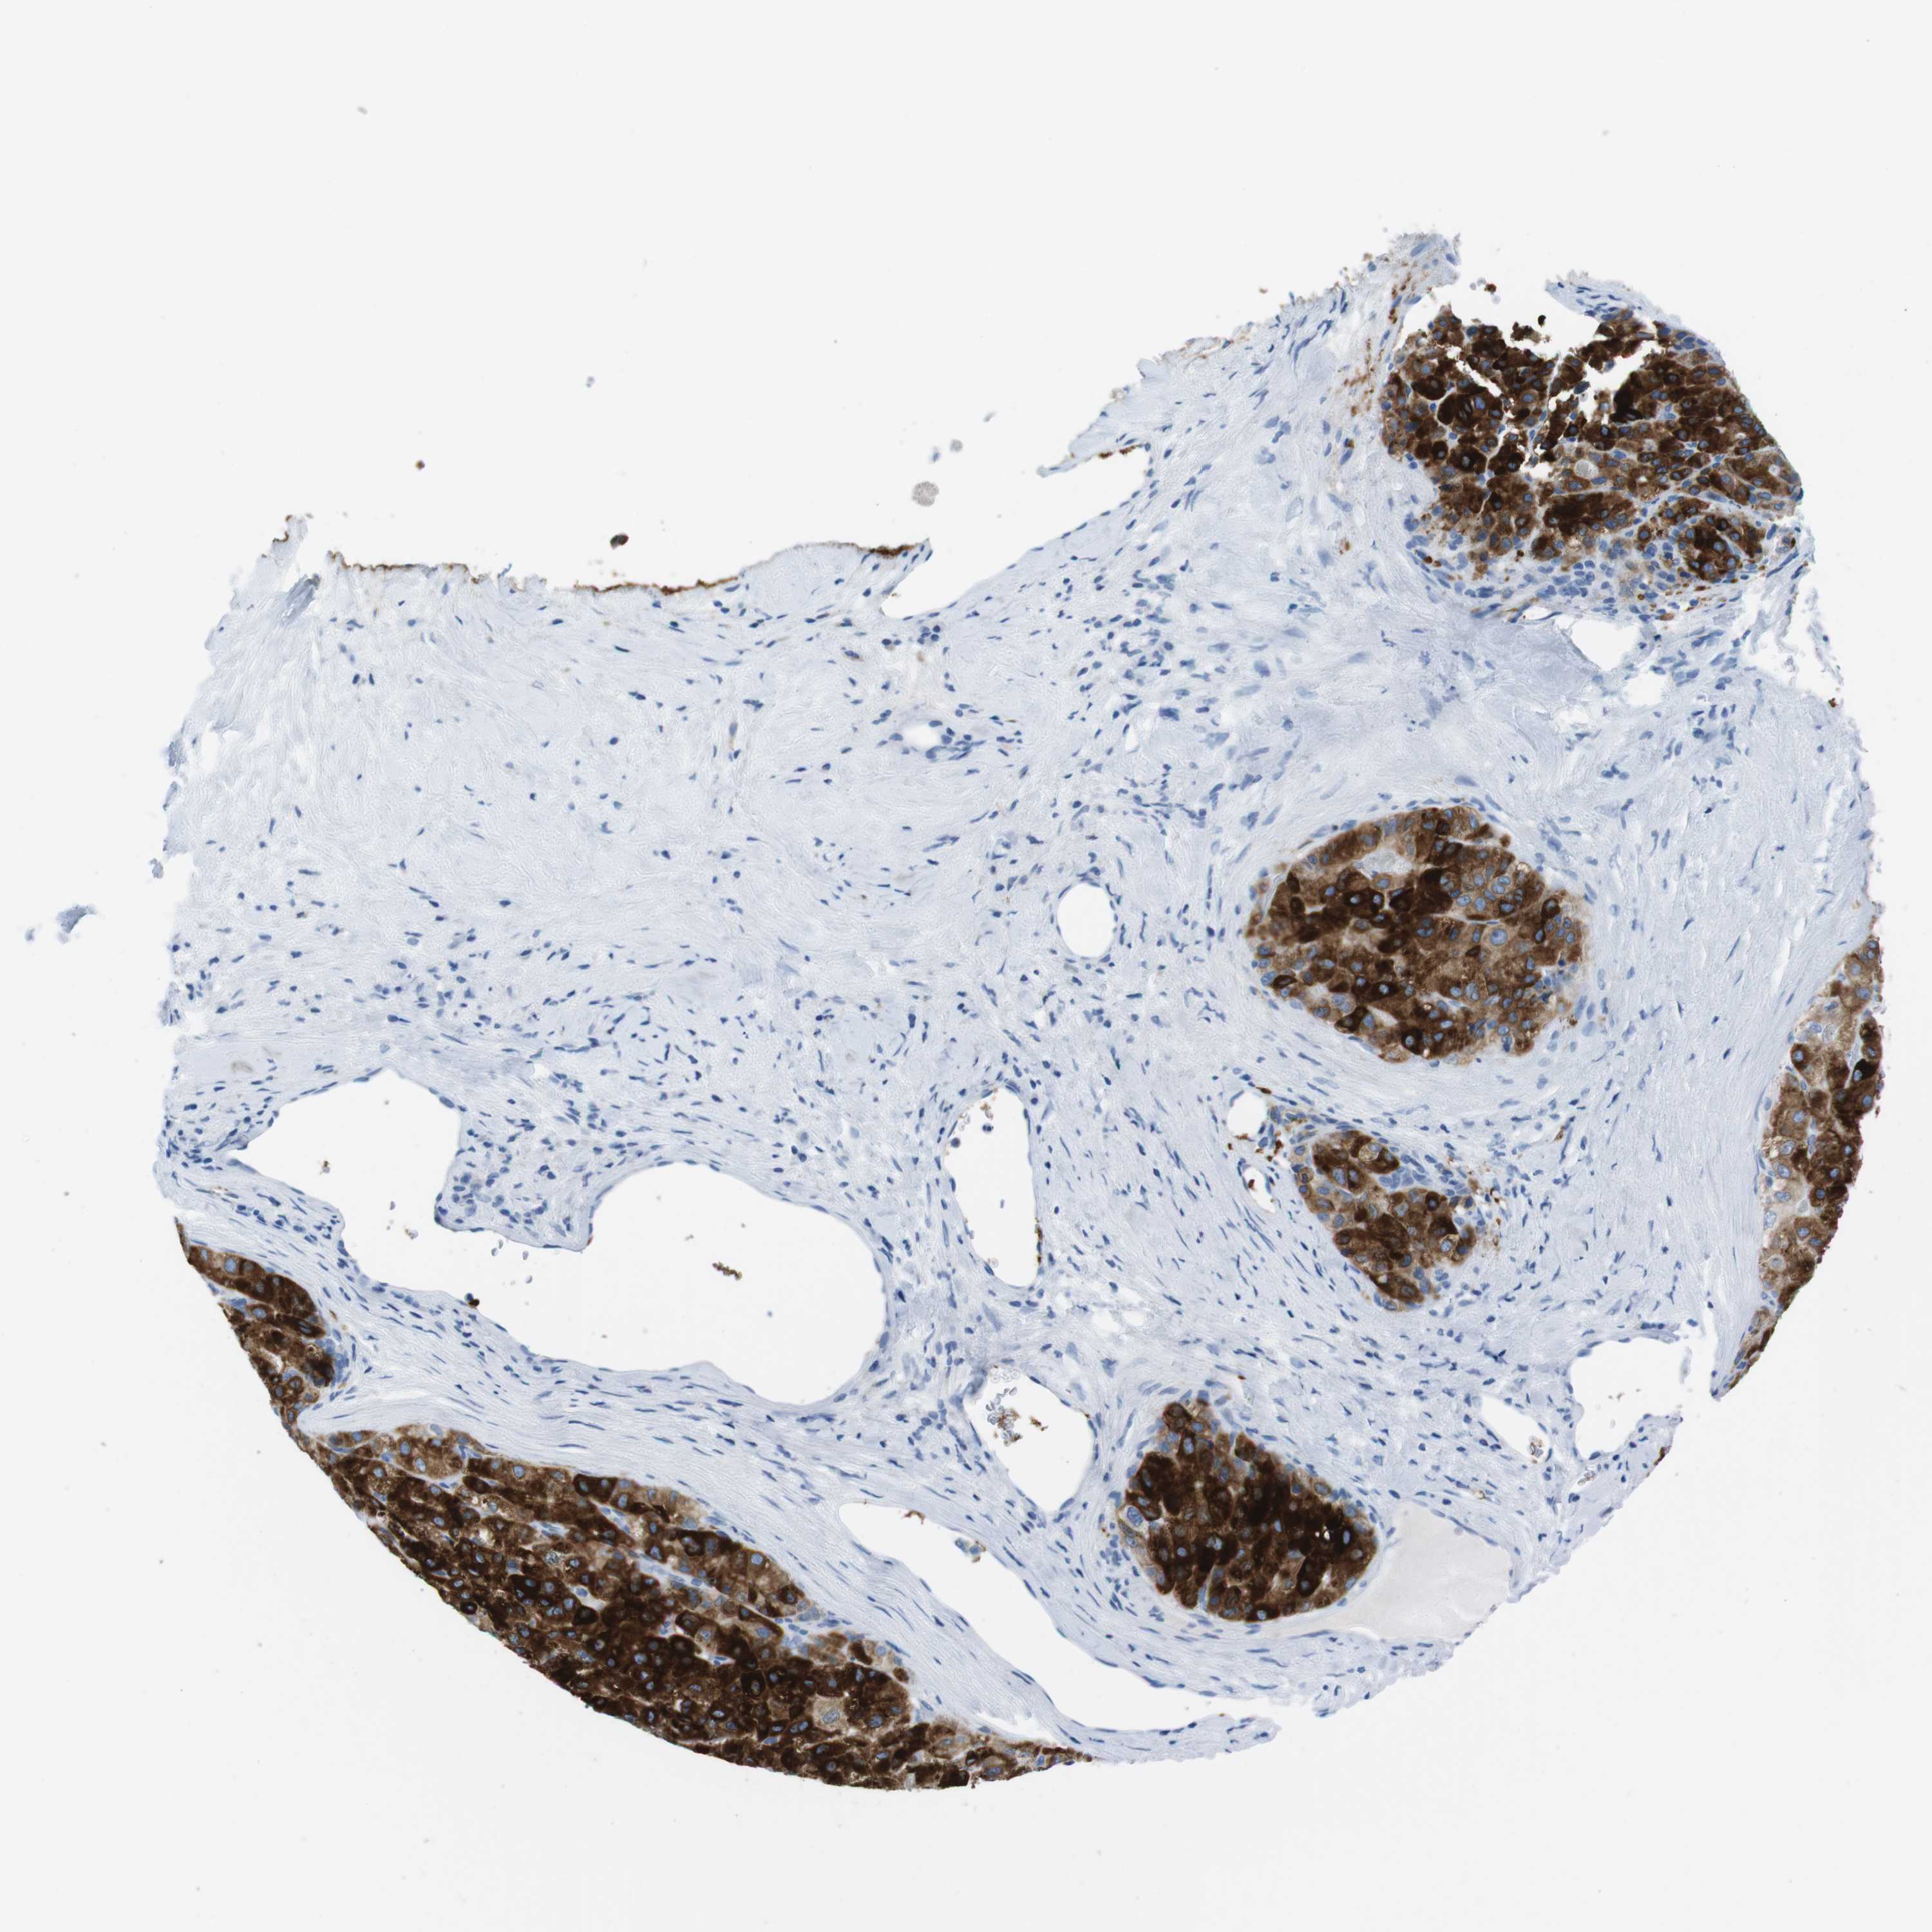

LIVER CANCER - Protein expressioni

A mouse-over function shows sample information and annotation data. Click on an image to view it in a full screen mode. Samples can be filtered based on level of antibody staining by selecting one or several of the following categories: high, medium, low and not detected. The assay and annotation is described here.

Note that samples used for immunohistochemistry by the Human Protein Atlas do not correspond to samples in the TCGA dataset.

Antibody stainingi

Antibody staining in the annotated cell types in the current human tissue is reported as not detected, low, medium, or high, based on conventional immunohistochemistry profiling in selected tissues. This score is based on the combination of the staining intensity and fraction of stained cells.

Each image is clickable and will lead to virtual microscopy that enables deeper exploration of all samples and also displays staining intensity scores, fraction scores and subcellular localization as well as patient and tissue information for each sample.

Antibody HPA015066

Antibody CAB016123

Staining

High

Medium

Low

Not detected

Intensity

Strong

Moderate

Weak

Negative

Quantity

>75%

75%-25%

<25%

None

Location

Nuclear

Cytoplasmic/membranous

Cytoplasmic/membranous,nuclear

Cholangiocarcinoma

Carcinoma, Hepatocellular, NOS